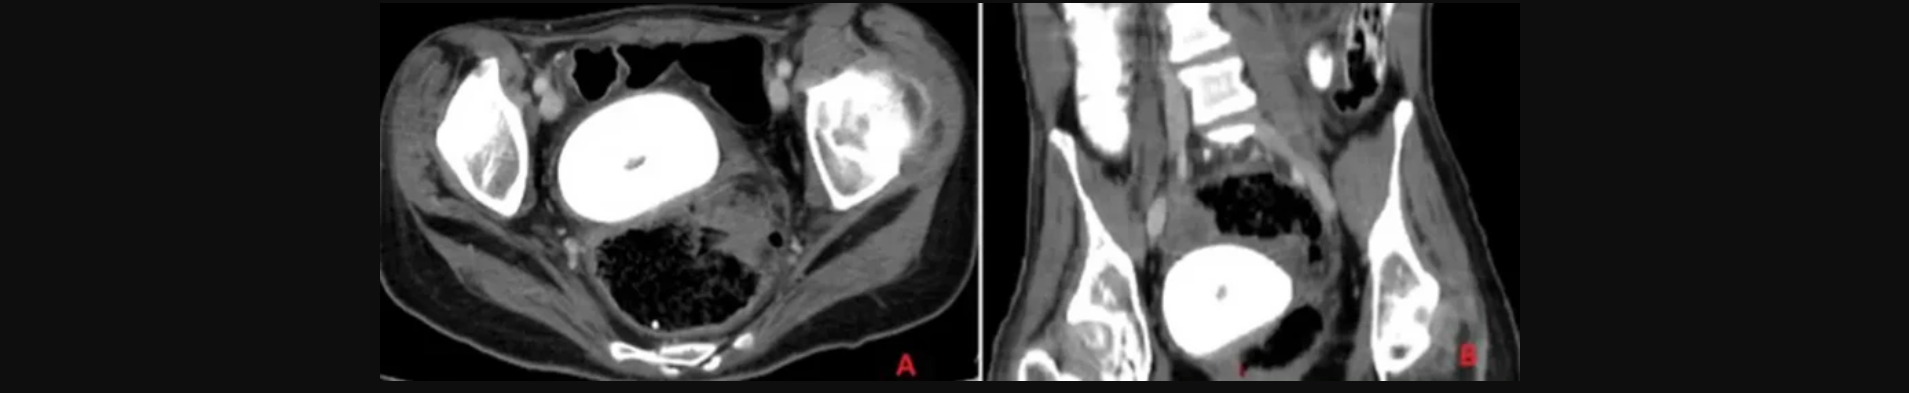

Τα συμπτώματα παρατηρήθηκαν τρεις ημέρες πριν η ασθενής μεταφερθεί εσπευσμένα στη ΜΕΘ. Είχε πυρετό, ρίγη, εμετούς, πόνους στην κοιλιά και μειωμένη όρεξη. Η αξονική τομογραφία σε λεκάνη και στην κοιλιά αποκάλυψε τον λόγο.

Το μέγεθος ήταν τόσο μεγάλο που πίεζε την ουροδόχο κύστη της γυναίκας, κάτι που οδήγησε σε ακόμη μεγαλύτερη διαρροή ούρων.